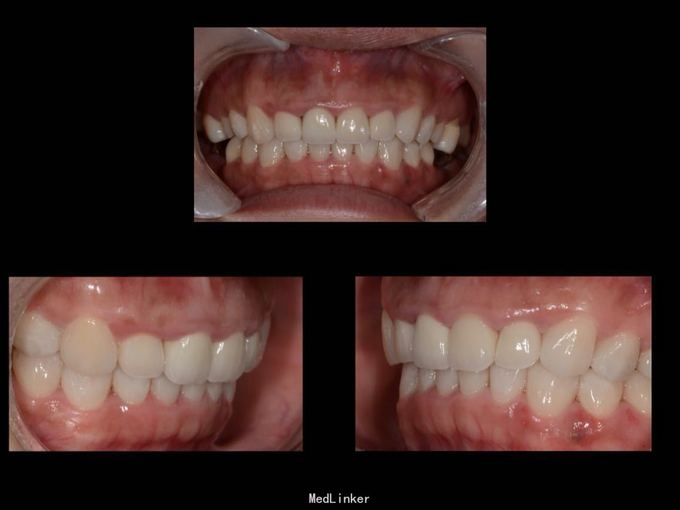

11 12 21 22死髓牙,不良修复体,牙龈炎 36 37 46 47残根 牙列不齐 处置:全口洁治。 比色,拍照,取模型做蜡型。 拆除旧修复体,拆桩核,做根管治疗,纤维桩修复,牙体预备,取模,做临时冠,粘固。11 12 21 22全瓷冠修复,13 14 23 24 31 32 33 34 41 42 43 44瓷贴面修复。

1.旧修复体覆合大,11 212 21 22龈缘位置较低且不对称,能做冠延长协调红白美学,更好 2.拆旧桩核要小心根折,用超声振动,一点一点拆.11桩核粘固比较牢固,根尖炎,定期观察行根尖手术倒充填。 3贴面的粘接,耐心